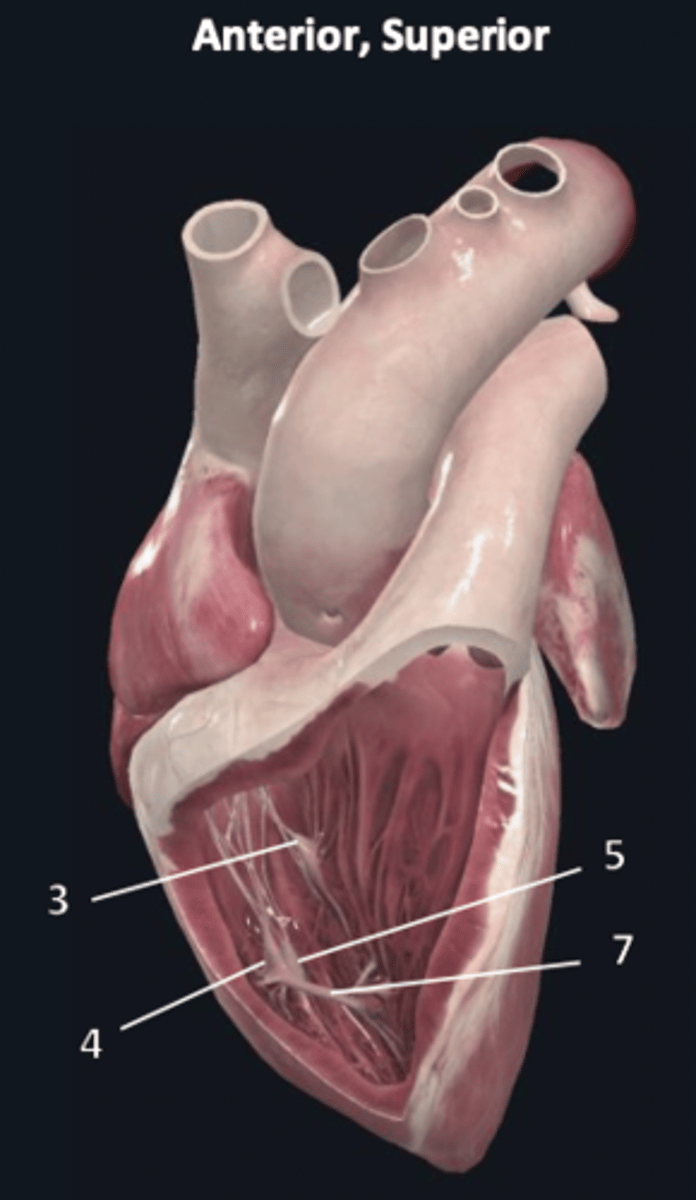

left atrium

1

left auricle

2

left ventricle

3

trabeculae carneae

4

inferior papillary muscle

5

superior papillary muscle

6

chordae tendineae

7

left atrioventricular valve

8 (opening)

aortic semilunar valve

9 (opening)